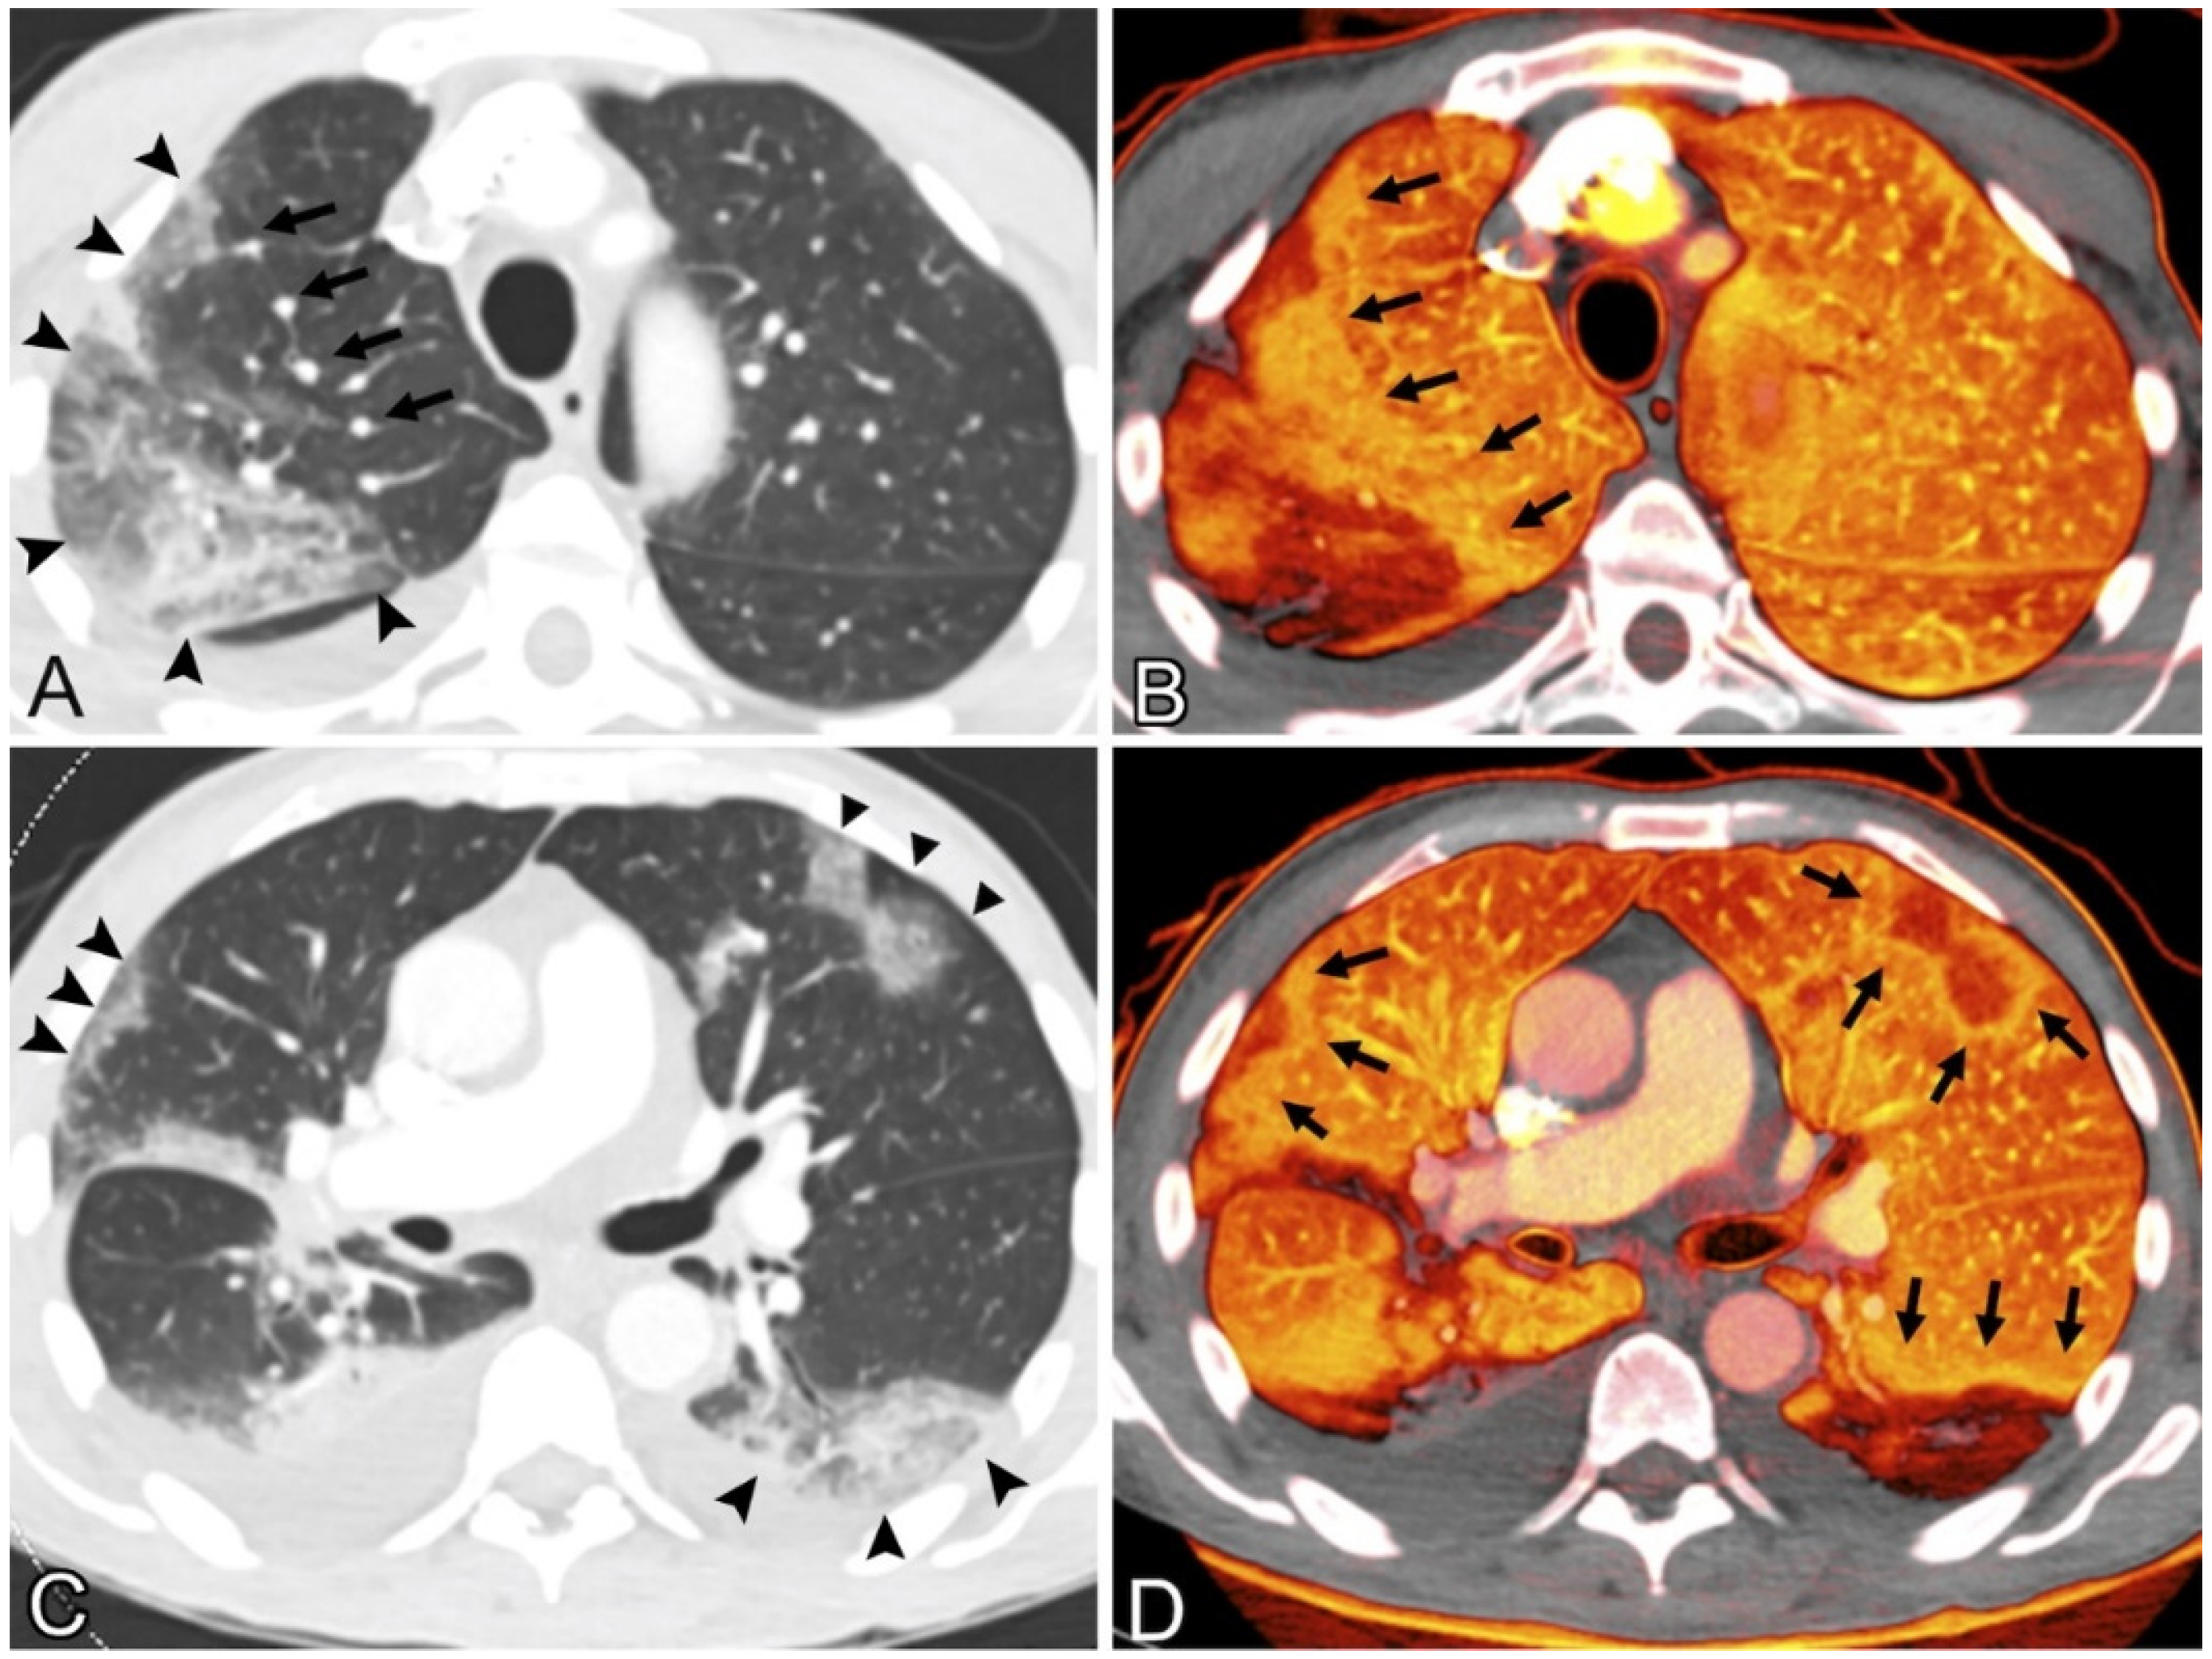

Pulmonary CT Images

| 2 | Lang et al. [82] (2020) | 45 | LBBM | Cancer | In COVID-19 pneumonia, pulmonary vascular anomalies such as vessel hypertrophy and regional mosaic perfusion patterns are frequent. | Pulmonary vascular dilatation can occur not just within lung opacities, but also in a regional pattern outside of parenchymal opacities, and it can even affect the subpleural lung. | CT | NR |

| 4 | Lins et al. [94] (2020) | NR | LBBM | NR | COVID-19 etiology involves pulmonary hemodynamic changes in the lung. | The pulmonary arterial density and tiny blood vessel volume were determined. | CT | NR |

| 9 | Scholkmann et al. [99] (2021) | 01 | LBBM | NR | Although focal vessel enlargement within ground-glass opacities was described in early imaging investigations of COVID-19, we have noted additional extensive vascular abnormalities. | vasculopathy was a direct viral effect on endothelial cells or perivascular inflammation | CT | NR |

- Lang, M.; Som, A.; Carey, D.; Reid, N.; Mendoza, D.P.; Flores, E.J.; Li, M.D.; Shepard, J.-A.O.; Little, B.P. Pulmonary vascular manifestations of COVID-19 pneumonia. Radiol. Cardiothorac. Imaging 2020, 2, e200277. [Google Scholar] [CrossRef] [PubMed]